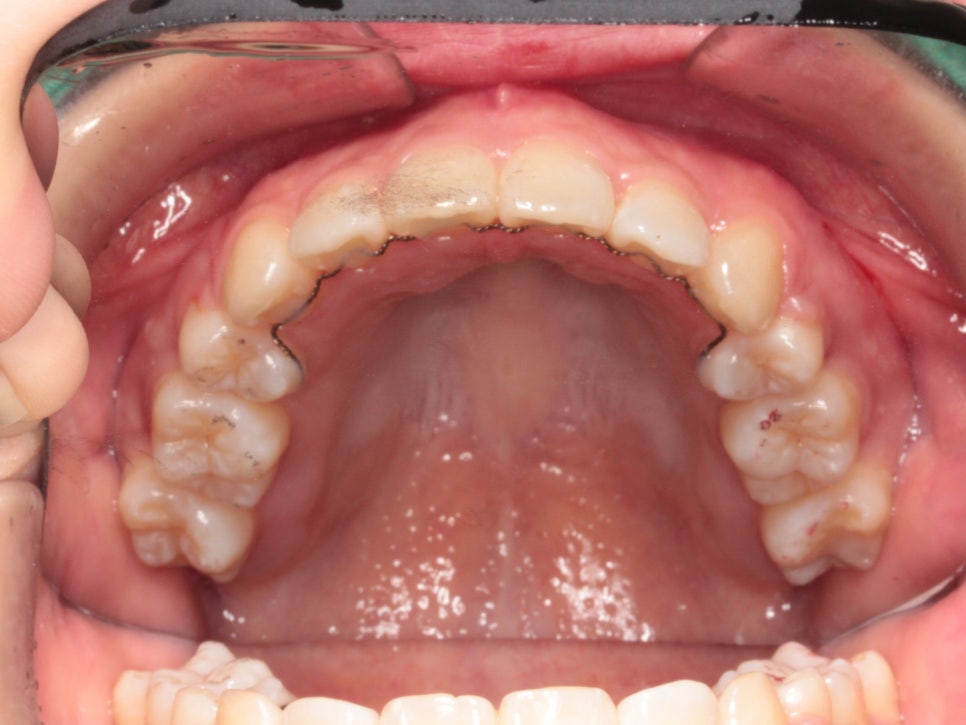

미니스크류를 식립 후 바로 찍은 사진입니다.

총 6개의 미니스크류를 식립하고 치료를 했습니다